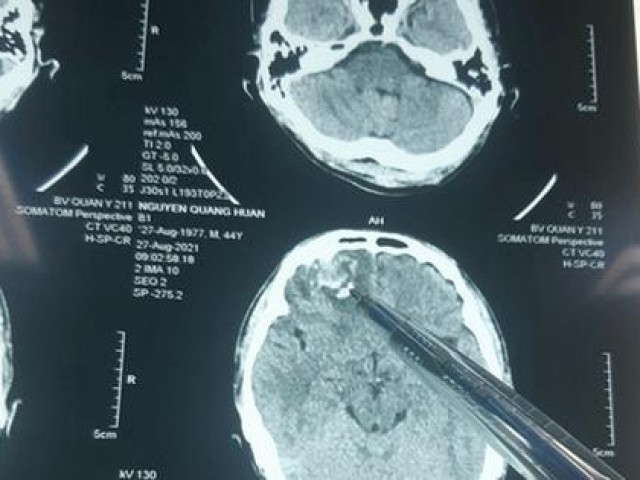

Mặc dù ông Khoa bỏ chạy nhưng các đối tượng vẫn đuổi theo, dùng hung khí tiếp tục đánh ông Khoa bị thương nặng. Khi Công an xã Châu Phong đến hiện trường thì nhóm của Tín bỏ trốn.